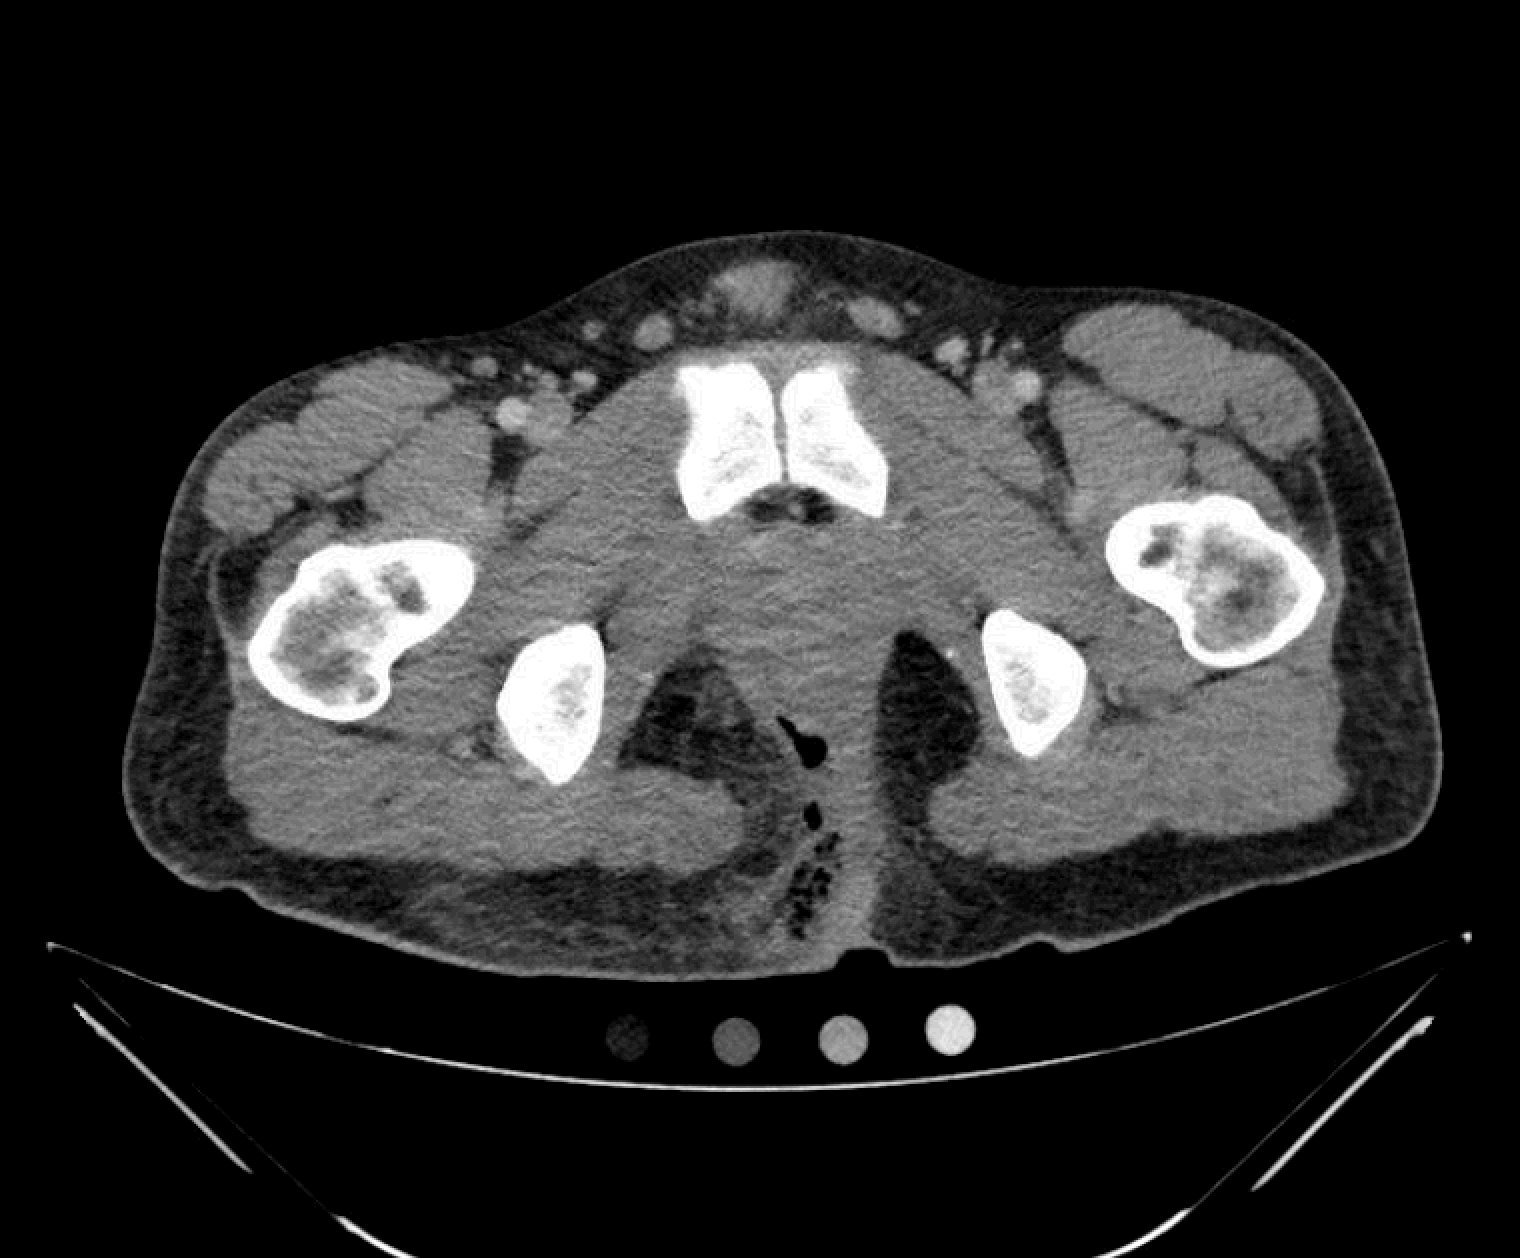

The computed tomography (CT) of the abdomen and pelvis revealed significant subcutaneous gas tracking along the perineum and right gluteal region (orange outline) into the scrotum with associated scrotal edema (yellow arrow) and subcutaneous inflammatory fat stranding of 0.92 cm (red arrow) consistent with Fournier’s gangrene. There is early fluid loculation along the right medial gluteal cleft of 5.85 cm (green arrow) without a sizeable drainable abscess seen.